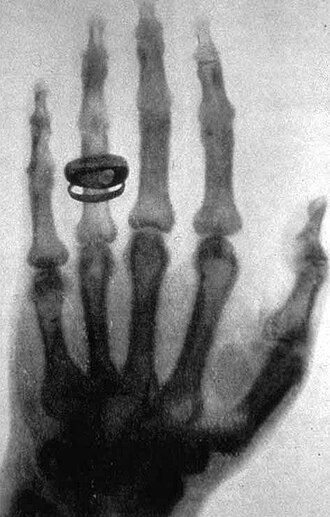

Valovi svjetlosti i elektromagnetski valovi imaju ista osnovna svojstva i šire se istom brzinom (brzina svjetlosti). Između njih nema nikakve razlike u njihovim fizičkim svojstvima, već se samo razlikuju u valnoj duljini, odnosno frekvenciji. Ogib, interferencija i polarizacija su pokazali da je svjetlost transverzalni val. Kod elektromagnetskog vala električno titranje je okomito na magnetsko, pa se te dvije promjene šire u prostor okomito na smjer svoga kretanja. Prema tome je i elektromagnetski val također transverzalno titranje. Pokusi pokazuju da električne promjene u elektromagnetskom valu djeluju na fotografsku ploču i na vidni živac u našem oku, pa imamo osjet svjetla. Sve nas to upućuje na to da su vidljivi valovi svjetlosti, kao i infracrvene, ultraljubičaste, rendgenske i gama zrake također elektromagnetski valovi, samo mnogo manje valne duljine. O valnoj duljini ovise njihova posebna svojstva. Svi valovi raspoređeni po svojoj valnoj duljini čine elektromagnetski spektar.